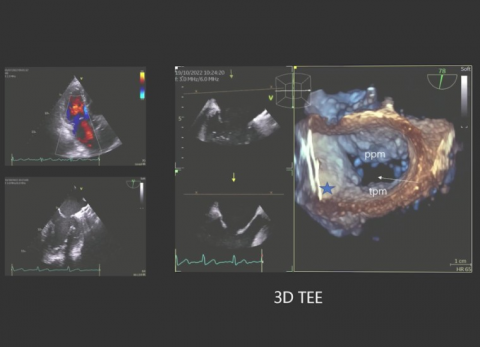

prof. dr hab. n. med. Jarosław KasprzakDane kliniczne:Pacjentka z niewydolnością sercaRozpoznanie główne:Kardiomiopatia przerostowa z zawężaniem drogi odpływu lewej komoryPoruszane zagadnie...